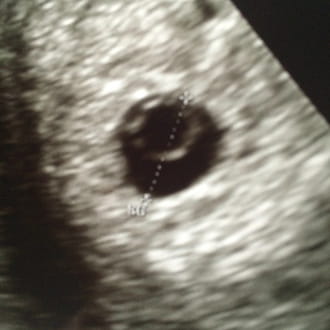

hola necesito una orientación. Estoy embarazada en la semana numero 6 y aun no aparece el embrion ni latidos. Estoy preocupada por que el doctor dijo que era un embarazo huero o huevo huero, ayer empece a sangrar fui a urgencia y me dijeron k era aborto retenido el saco no presenta Signo de desprendimiento pero aun o hay embrion k espere 10 días más para otra eco. Habrá esperanza aun de que aparezca embrion o debo abortarlo ? Me da miedo el raspaje y deseamos un bebe con mi pareja que puedo hacer ??